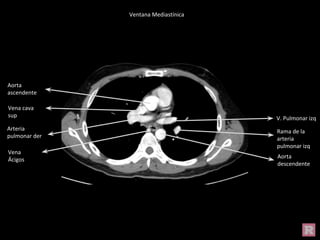

Aorta

descendente

V. Pulmonar izq

Arteria

pulmonar der

Rama de la

pulmonar izq

ascendente

Vena cava

sup

Vena

Ácigos